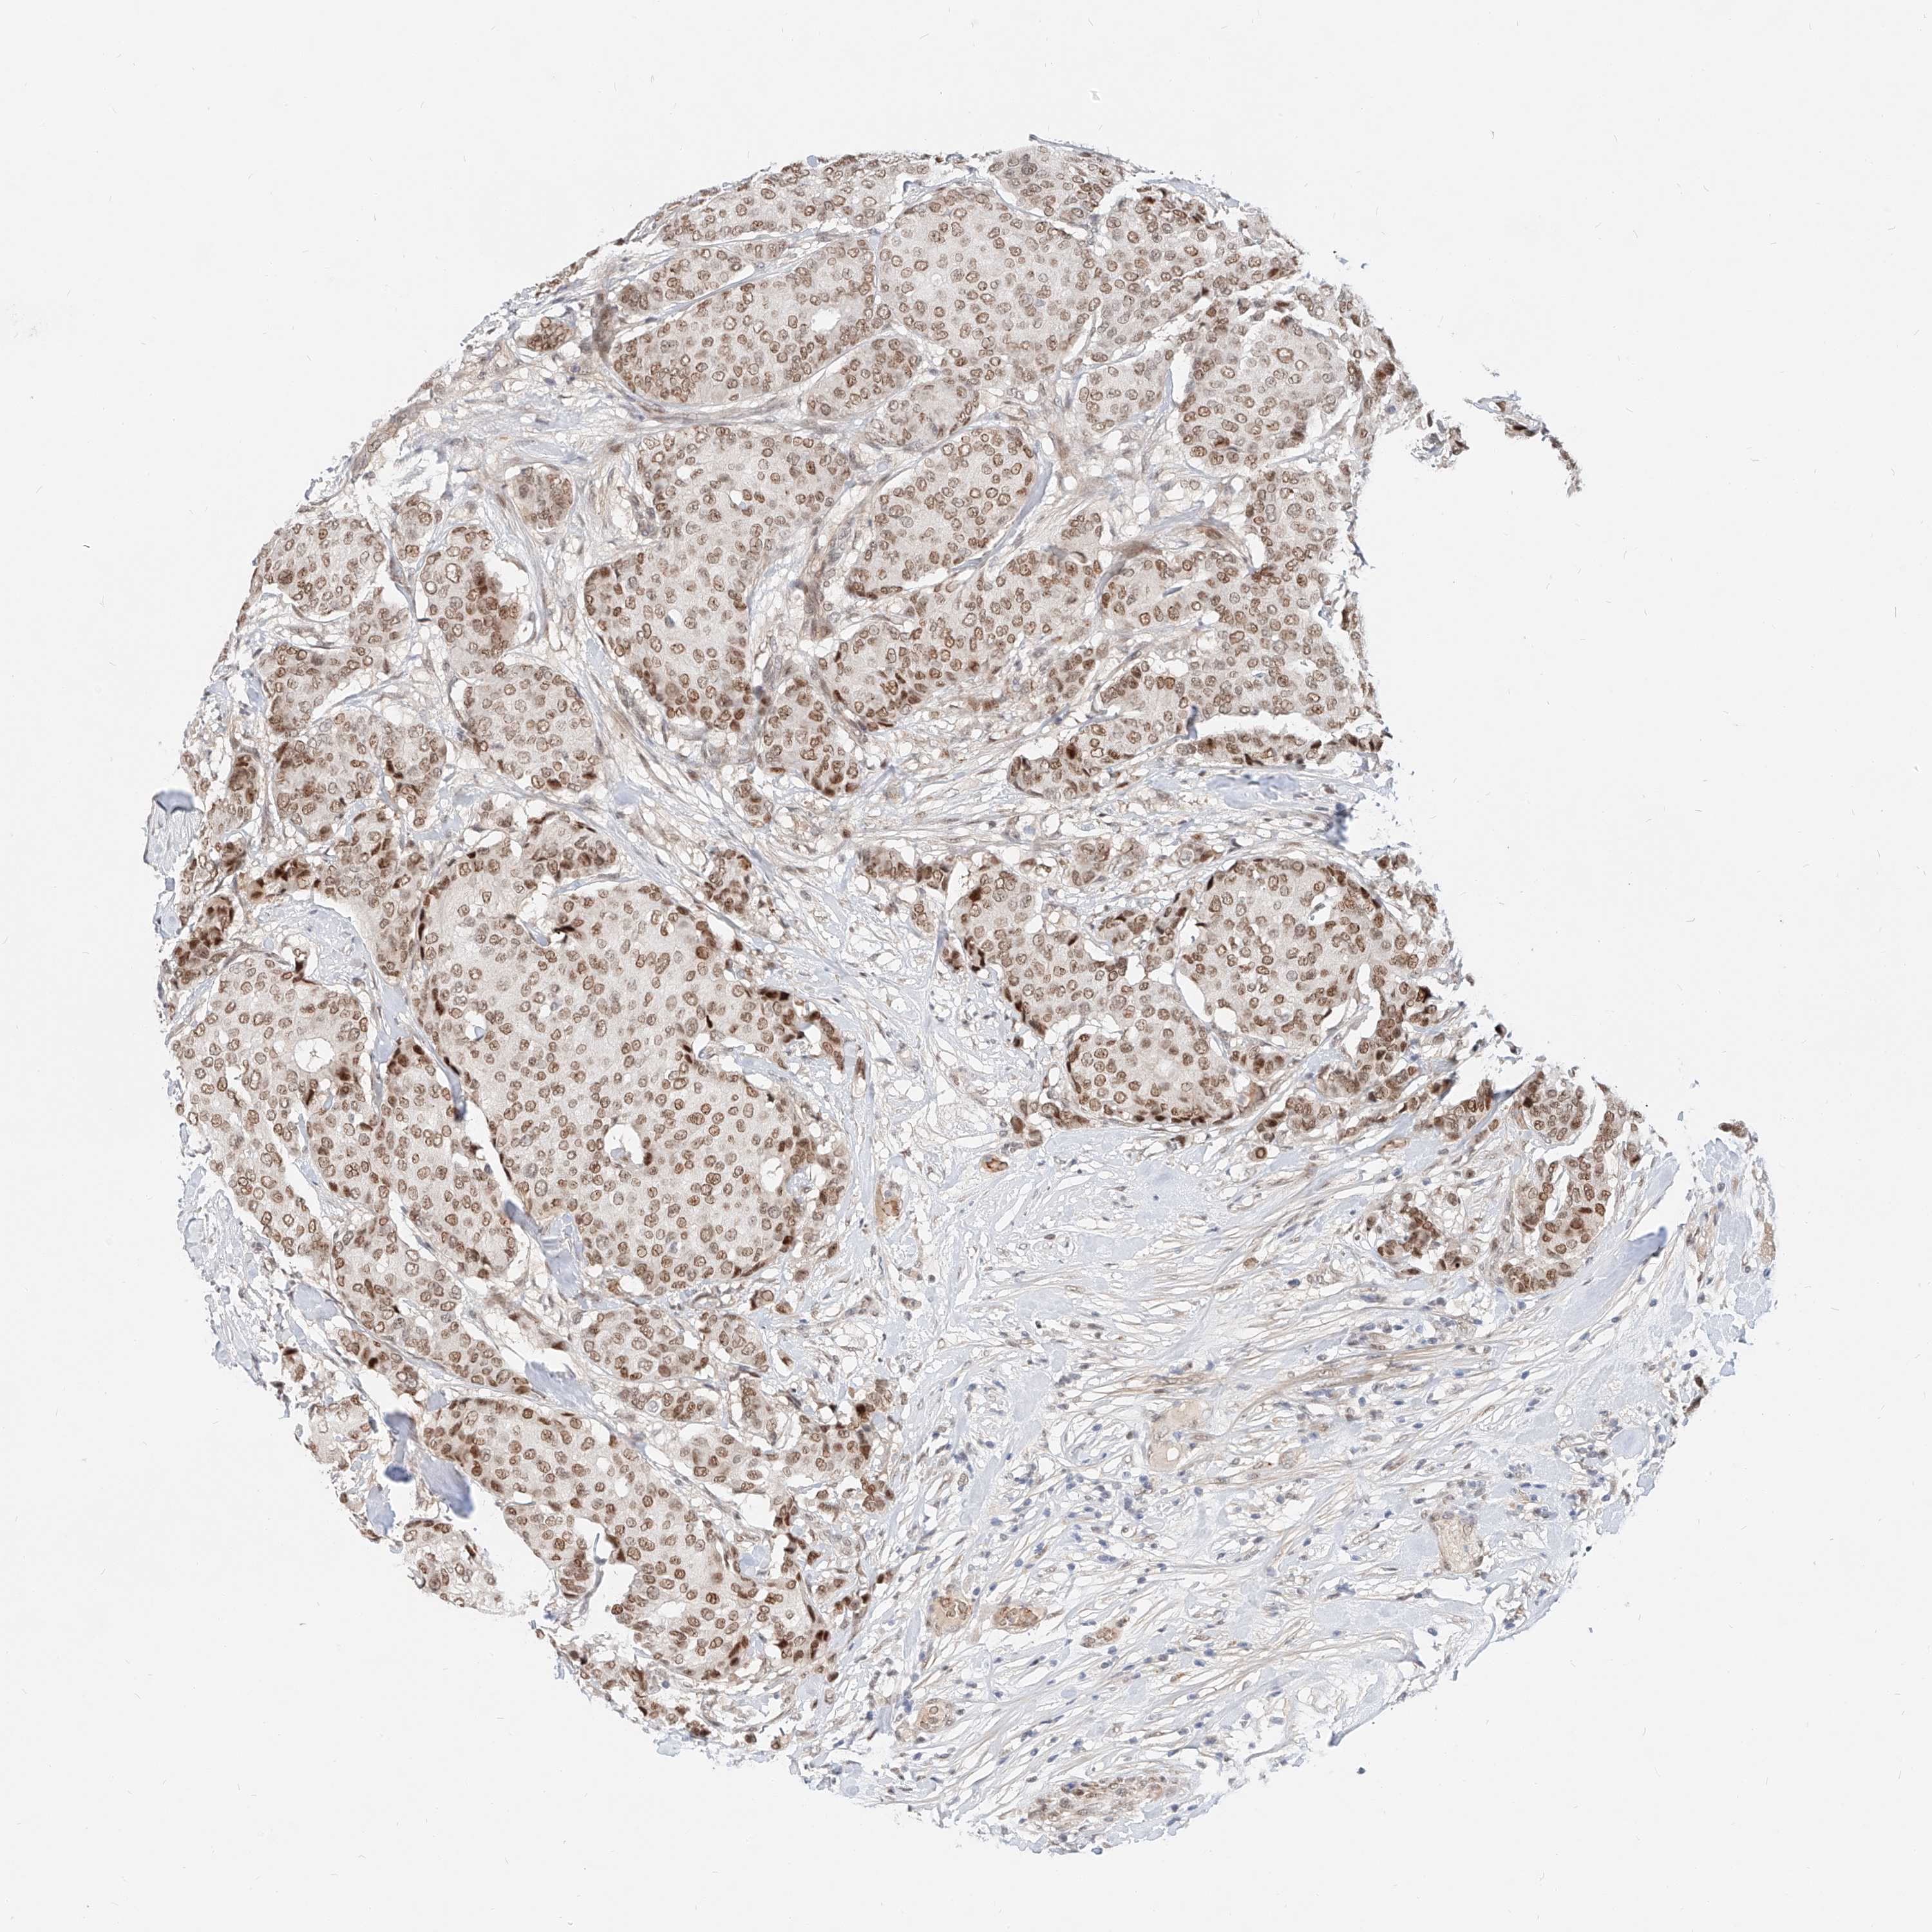

BRCA TCGA BRCA VALIDATION PROTEIN EXPRESSION

ANTIBODIES

AND

VALIDATION